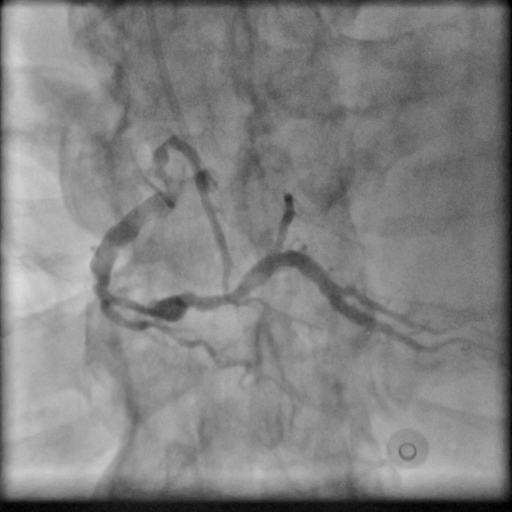

Coronary angiography showed 2-vessel coronary artery disease with severe stenosis in mid to distal-RCA and TIMI-2 flow. Small balloon pre-dilatation, followed by manual IVUS pullback performed. We noted mostly fibrous plaques but some lipid pools along the vessel with a short segment of heavy calcification. Thus an embolic protection device was placed smoothly in distal-RCA. Next lesion preparation with a 3.5x30mm balloon. Unfortunately we failed to notice incomplete balloon expansion in mid-RCA.

Using an AL1 guiding catheter, we navigated to the RCA-PDA. We performed balloon dilatation of the lesions in the RCA-M to RCA-D. IVUS with manual pullback revealed fibrous plaques with lipid pools and a glimpse of circumferential calcification in the RCA-M. We positioned the Spider FX embolic protection device with its filter basket in the RCA-D. Lesion preparation was done with a Euphora 3.5x30mm balloon. Stent deployment involved deep seating and using a guide extension catheter (GEC) to deploy an Ultimaster-Nagomi 3.5x44mm stent from RCA-M to RCA-D and another Ultimaster-Nagomi stent in the RCA-M. Notable underexpansion was observed in the middle part of the RCA-M stent . Post-dilatation was performed with an NC Accuforce 4.0x15mm balloon at 28 ATM. However, the RCA-M remained non-dilatable with persistent stent underexpansion. IVUS confirmed extensive circumferential calcification in the RCA-M. Despite multiple attempts using the GEC and balloon anchoring technique, we couldn't retrieve the Spider catheter's basket. We then used an intravascular lithotripsy balloon to deliver shockwaves to the proximal calcium ring, alternating with NC balloon inflations. Fortunately this inch-worm advance of the IVL achieved full stent expansion. Eventually, using an anchor balloon with GEC, we successfully retrieved the filter basket. The final angiography showed TIMI-3 flow in the RCA without any hemodynamic change throughout the procedure. A small emboli was found in the filter basket.